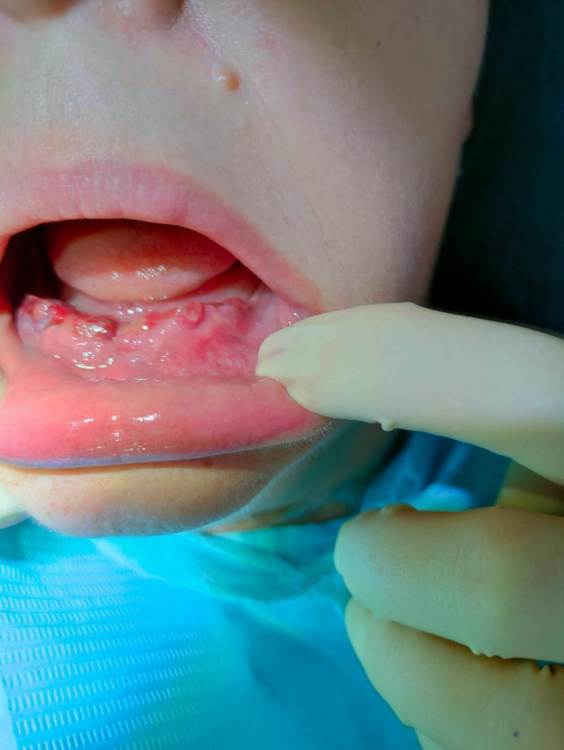

Irouil Опубликовано 12 апреля, 2023 Поделиться Опубликовано 12 апреля, 2023 Уважаемый коллеги! Встречал ли кто-то в практике случаи, когда в одной армированной временной дуге фейлили 5 из 6 винтов? Недавно со мной приключилась такая история: пациент, лет 60, из соматики только ИБС, но без терапии, был набор анализов перед операцией (общий, биохимия, коагуло - все, в принципе, в норме или практически в норме), генерализованный пародонтит, а/б интраоперационно, тотальное удаление, по 6 винтов на челюсть, длина винтов от 8 мм до 12 мм, торки 20-35, мульты, протез фрезерованная балка + акрил через 10 дней, 9 месяцев выждали. 6 нижних винтов интегрированны, 5 из 6 верхних - нет! Интегрирован винт в позиции 2.4, слева от него 2.6 - нет, ну и 4 штуки справа (6-4-2-2). У меня был один случай, когда протез вынулся со всеми винтами. У меня бывают случаи, когда 1 винт из дуги (обычно крайний) факапит. Но в данном кейсе я не могу понять одного - как мог интегрироваться 2.4, если вокруг него все "дышало"? В моем понимании имплантационной биомеханики это не укладывается. У кого какие будут идеи? Ссылка на комментарий